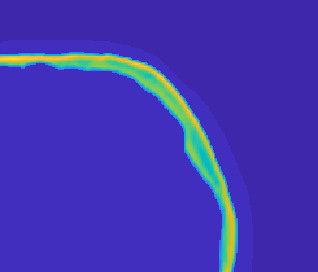

Model-based treatment planning for transcranial ultrasound therapy typically involves mapping the acoustic properties of the skull from an x-ray computed tomography (CT) image of the head. Here, three methods for generating pseudo-CT images from magnetic resonance (MR) images were compared as an alternative to CT. A convolutional neural network (U-Net) was trained on paired MR-CT images to generate pseudo-CT images from either T1-weighted or zero-echo time (ZTE) MR images (denoted tCT and zCT, respectively). A direct mapping from ZTE to pseudo-CT was also implemented (denoted cCT). When comparing the pseudo-CT and ground truth CT images for the test set, the mean absolute error was 133, 83, and 145 Hounsfield units (HU) across the whole head, and 398, 222, and 336 HU within the skull for the tCT, zCT, and cCT images, respectively. Ultrasound simulations were also performed using the generated pseudo-CT images and compared to simulations based on CT. An annular array transducer was used targeting the visual or motor cortex. The mean differences in the simulated focal pressure, focal position, and focal volume were 9.9%, 1.5 mm, and 15.1% for simulations based on the tCT images, 5.7%, 0.6 mm, and 5.7% for the zCT, and 6.7%, 0.9 mm, and 12.1% for the cCT. The improved results for images mapped from ZTE highlight the advantage of using imaging sequences which improve contrast of the skull bone. Overall, these results demonstrate that acoustic simulations based on MR images can give comparable accuracy to those based on CT.